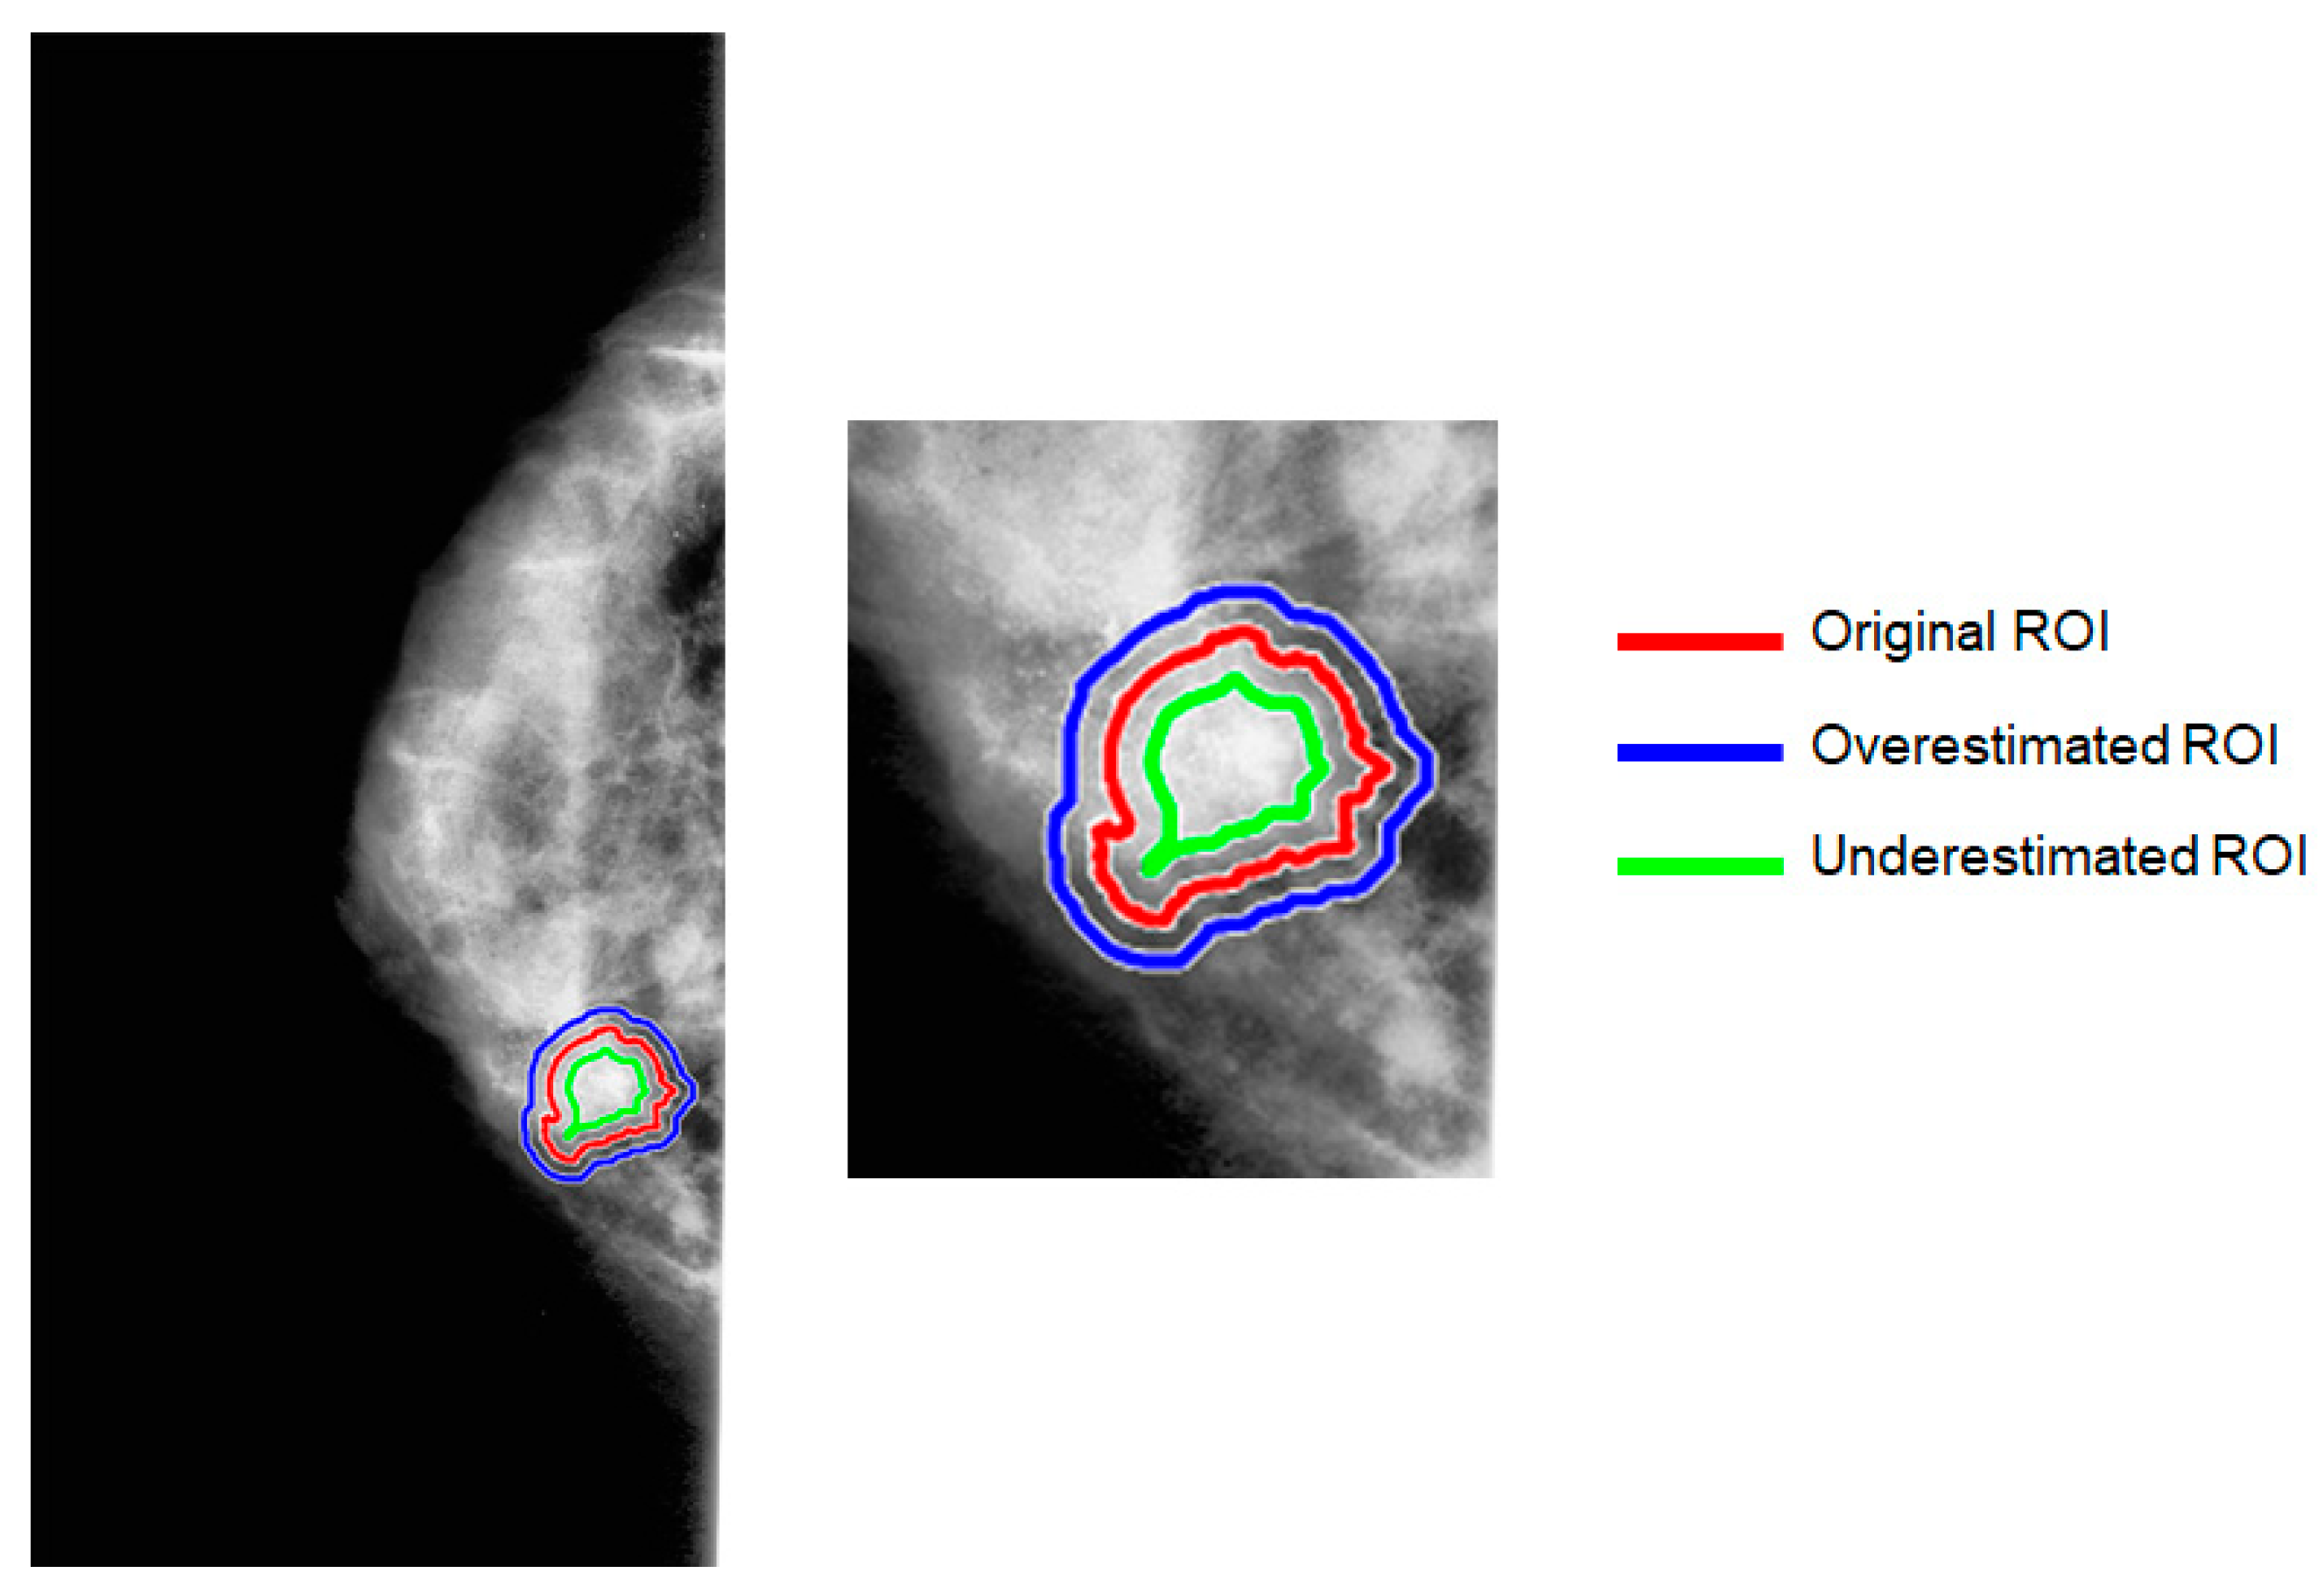

2.4. Generation of Artificial ROI